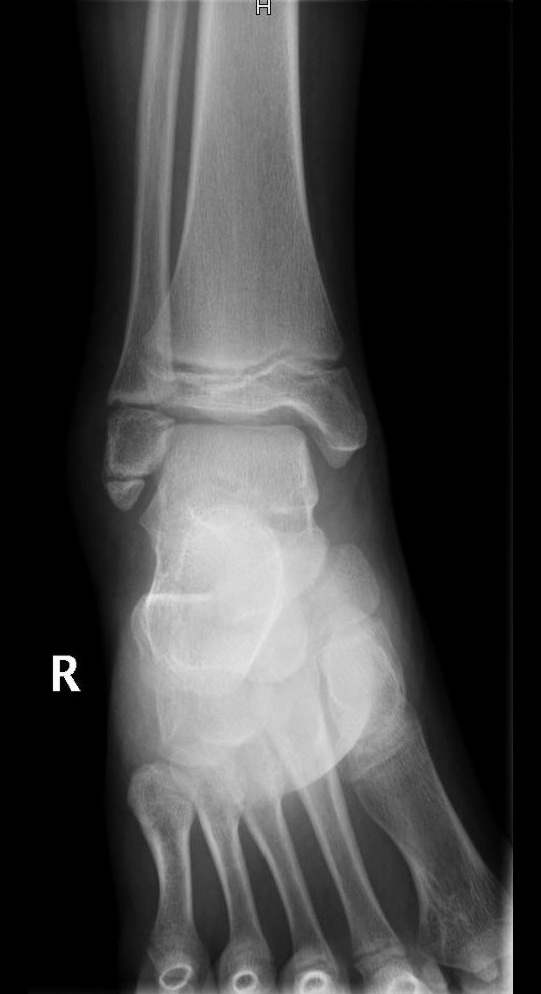

Niña de 11 años de edad sin antecedentes de interés que acude a Urgencias por dolor a nivel del maléolo externo del miembro inferior derecho tras un movimiento anómalo del pie con inversión del tobillo hace 2 días. Asocia tumefacción e impotencia funcional leves. Le han administrado analgesia en el domicilio sin mejoría. A la exploración, presenta tumefacción y dolor selectivo a la palpación del maléolo externo y los ligamentos peroneoastragalinos anterior y posterior. No crepitación ni resaltes óseos ni hematoma. No presenta limitación de la movilidad pasiva y si presenta limitación a la movilización activa por dolor. Se realiza radiografía anteroposterior (Figura 1) y lateral (Figura 2) del tobillo derecho.

Figura 1. Proyección anteroposterior.